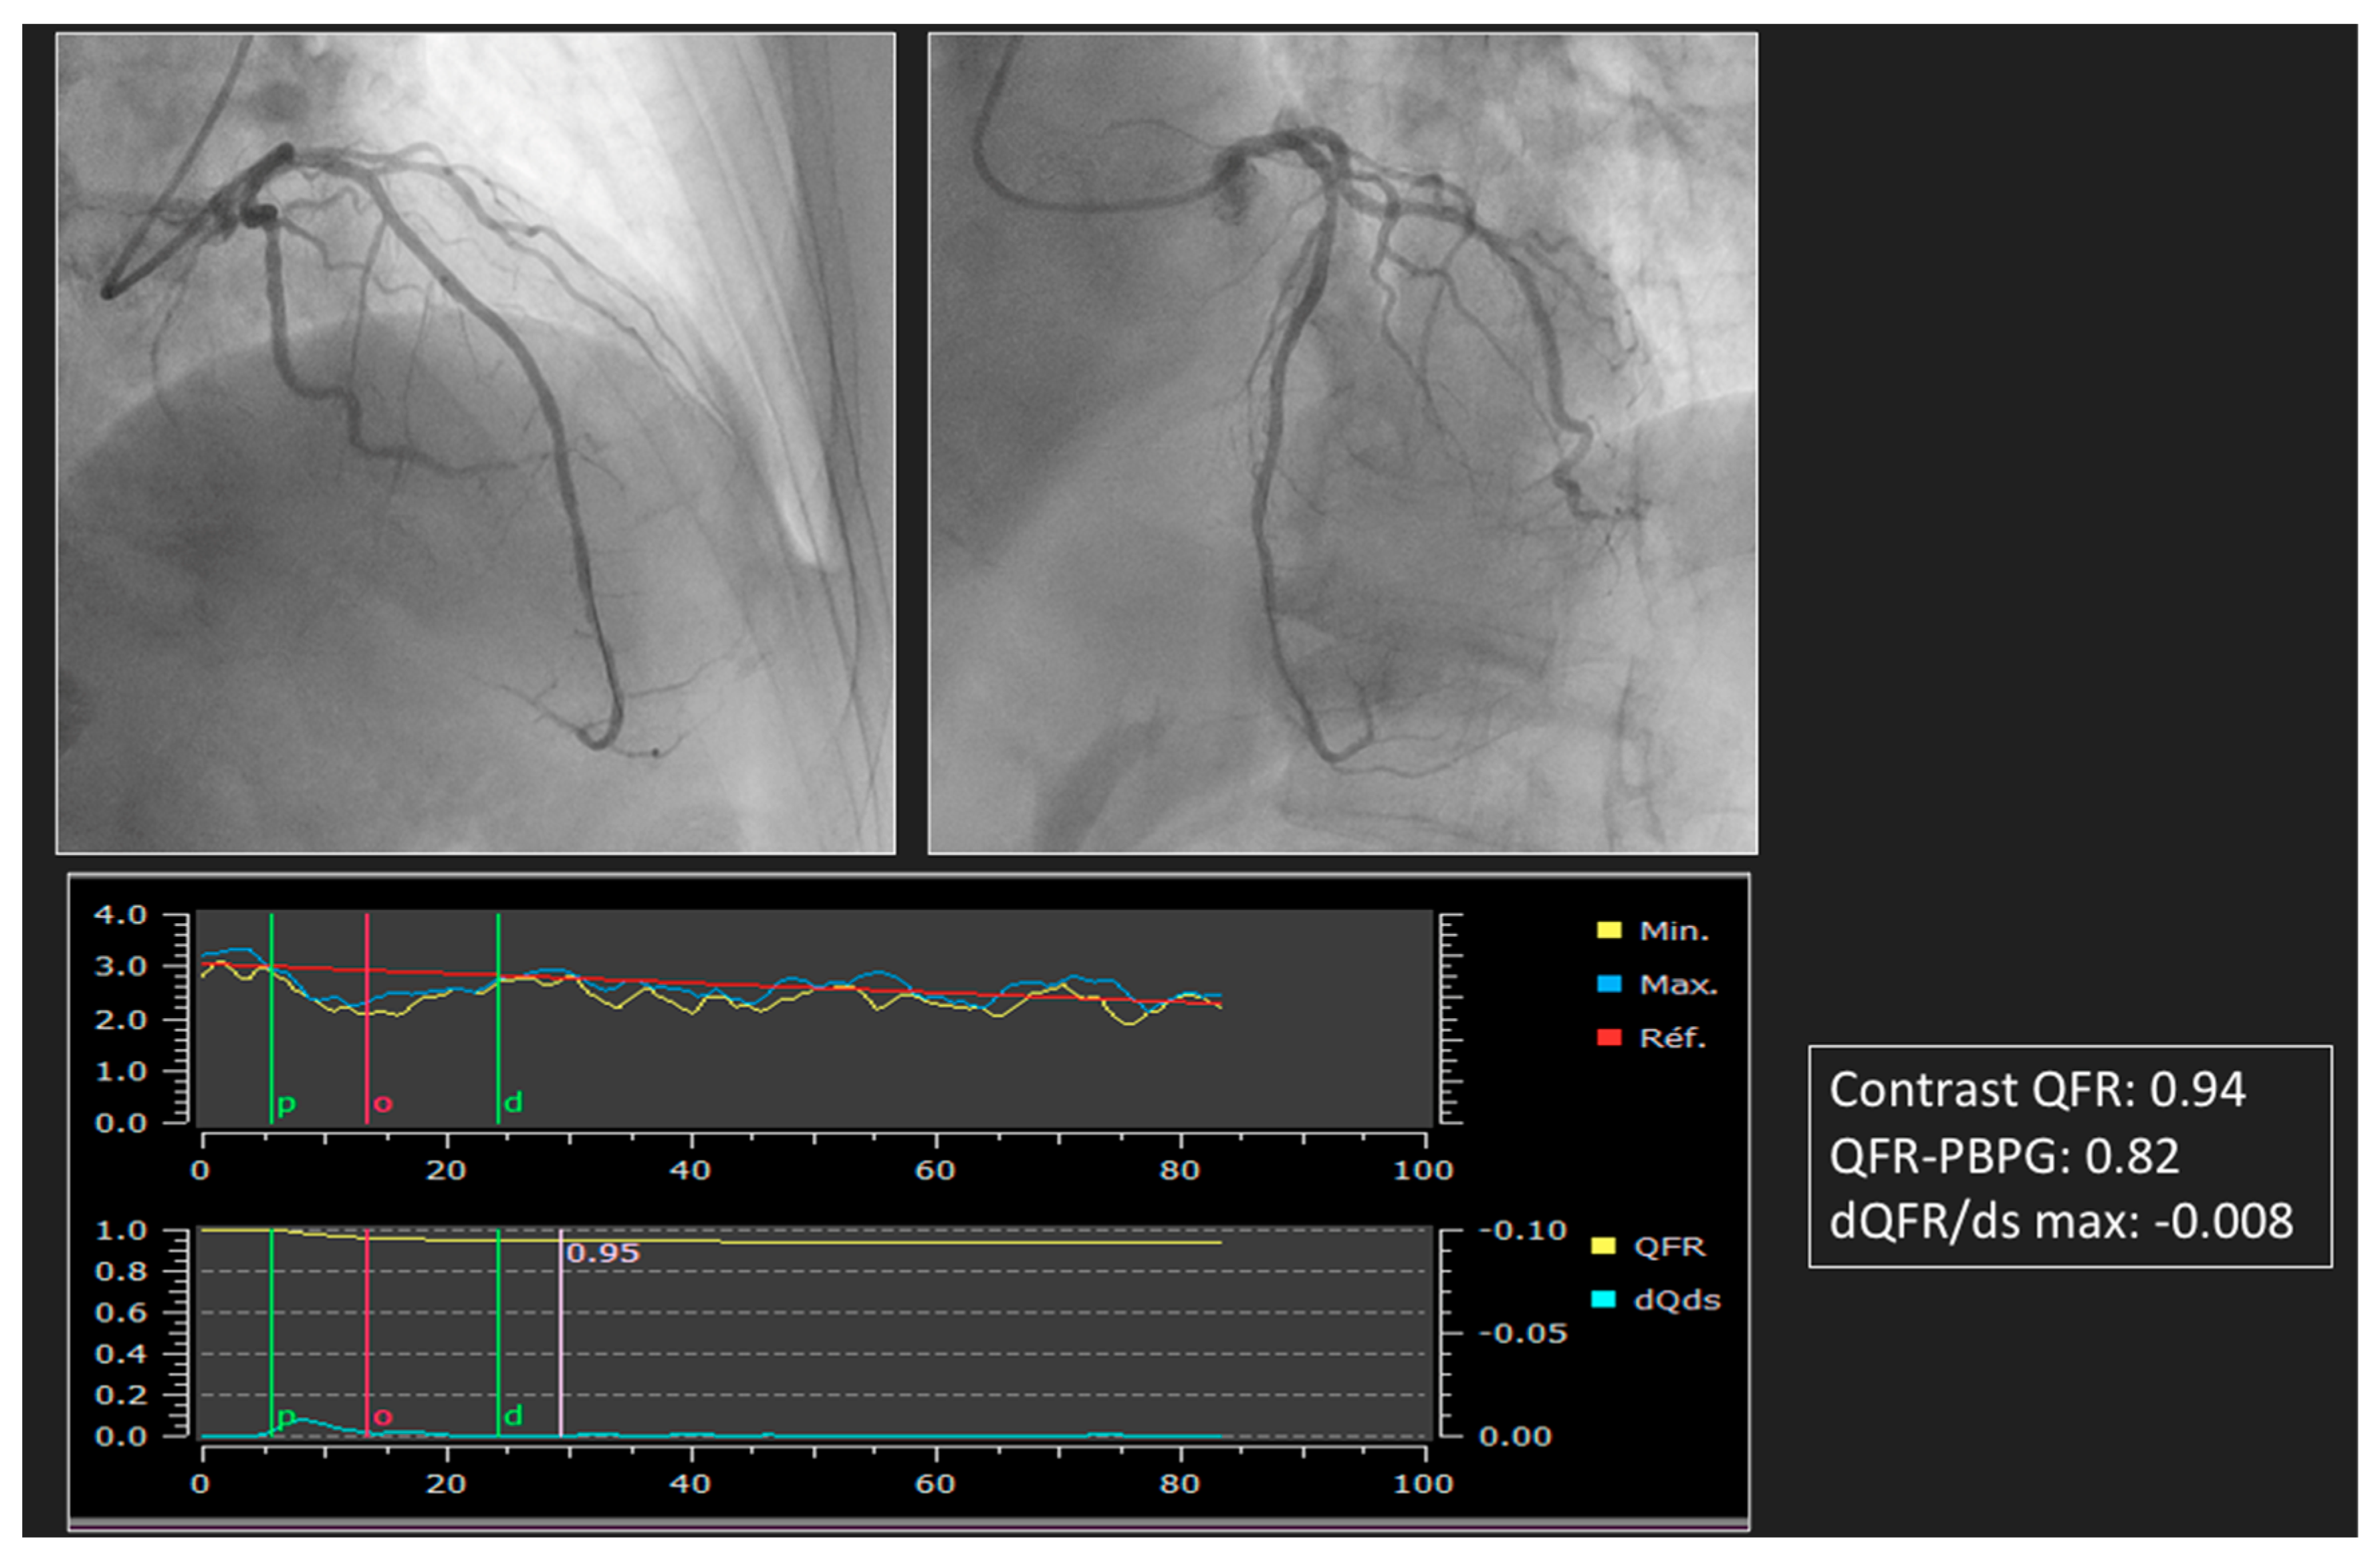

This problem can be circumvented by using angiography-derived FFR, which is free from variations in post-PCI hemodynamic conditions. With angiography-derived FFR, the analysis will not take into account these acute post-PCI hemodynamic disturbances. The measurement will therefore be much more reproducible and will not require time for normalization. The prognostic value of post-PCI QFR was demonstrated in a retrospective study enrolling patients treated with state-of-the-art PCI for de novo three-vessel disease [28]. In the prospective HAWKEYE study, it was shown that a post-PCI QFR ≤ 0.89 was independently related to a poor prognosis. In this study, the rate of suboptimal PCI was 16%, and those were associated with an unfavorable outcome. Among these 16%, subjective analysis of the pullback curve after PCI identified a focal drop inside the stent in 13% of cases and outside the stent in 32%. A total of 34% showed a steady and progressive decrease in the QFR curve, suggestive of diffuse disease, and 21% showed a combination [29]. All invasive coronary physiology indexes used to characterize post-PCI abnormalities have their surrogates derived from angiography [52]. After PCI, the software can generate a QFR pullback curve but also QFR-PBPG and dQFR/ds. A focal lesion is defined by a QFR abrupt pressure drop-down with ΔQFR > 0.05 in <10 mm [53] or QFR-PBPG > 0.78 with major gradient defined by dQFR/dt ≥ 0.005/mm. The residual disease patterns, particularly predominantly diffuse with major gradient, were independently associated with VOCO at 2 years [30]. If suboptimal PCI is found (QFR ≤ 0.89), the causes must be identified by QFR virtual pullback, QFR-PBPG, and dQFR/ds in order to understand whether the problem is focal (such as stent edge dissection or under expansion, or significant stenosis located proximally to the target PCI) and whether an additional stent is required. In such cases, endocoronary imaging such as IVUS or OCT may be used. Figure 3 shows several indexes available after PCI. The amount of data in the PCI item are much less compared with other angiography-derived FFR, with only comparison studies of post-PCI FFR with post-CASS vFFR [31,32].

Figure 3.

Post-PCI index derived by angiography (post-PCI QFR, pullback QFR, QFR-PPG, dQFR/ds).